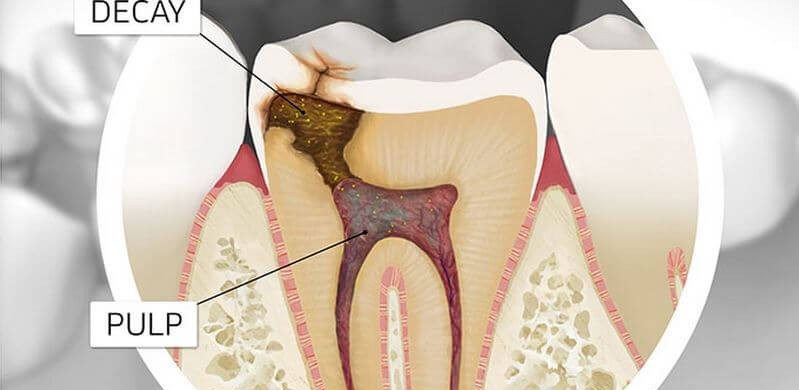

Tooth decay is the breakdown of the tooth’s structure and can impact both the enamel and the dentin layer of the tooth. Tooth decay happens when foods that contain carbohydrates (sugars and starches) remain on the teeth. The bacteria that lives in the mouth them digest these foods, turning them into acids.

A reaction occurs which combines the bacteria, acid, food debris, and saliva and turns them into plaque, which clings to the teeth. The acids in the plaque them begin to dissolve the teeth’s enamel, creating the holes which are commonly known as cavities.

Typically, amalgam fillings or glass ionomer cement restorations are used to treat tooth decay. An oral surgeon may also opt to install dental crowns or perform a root canal treatment to treat your tooth decay.